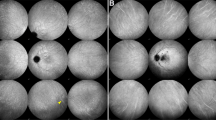

Thirteen consecutive eyes of 12 patients for whom fundus near-infrared fluorescence and 20° retinal sectional images were obtained using HRA2 and Spectralis OCT, respectively, 5 days after vitrectomy combined with ICG-assisted inner limiting membrane peeling for DMO. The relationship between the characteristics of the ICG hyperfluorescence and the cystoid spaces in the outer plexiform layer (OPL) on SD-OCT images was evaluated.

A total of 390 well-demarcated areas of ICG hyperfluorescence were delineated on 20° radial OCT scans dissecting the fovea 5 days after vitrectomy. The areas of ICG hyperfluorescence in the parafovea or perifovea were significantly smaller than those at the fovea. Most areas of hyperfluorescence were irregularly shaped in the parafovea and perifovea, whereas 18 of 38 areas of hyperfluorescence were round or oval at the fovea (P<0.001). SD-OCT delineated the cystoid spaces in the OPL in 73 areas of hyperfluorescence that were round or oval and accompanied by dark spots more frequently than that without cystoid spaces on OCT images (P<0.001 and P=0.002). Of the 123 cystoid spaces in the OPL on OCT images, 44 did not have ICG hyperfluorescence, had lower OCT reflectivity, and contained fewer hyperreflective foci than those with ICG hyperfluorescence (P<0.001 and P=0.020).